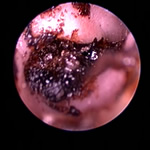

ワンちゃんでは外耳炎の診察が非常に多く、当院では1日10件以上診察することもよくあります。外耳炎の原因は様々ありますが、脂漏症、角化症のワンちゃんで最も多く、アトピー性皮膚炎でも外耳炎が起こります。飼主さまに食物アレルギーとの関連を聞かれますが、脂漏症、角化症、アトピー性皮膚炎に比べると食物アレルギーが原因であることは少ないです。そして、外耳炎が治りにくくなったり、発病するきっかけになるのが、日ごろの耳洗浄だと思っています。一方、ネコちゃんの耳の病気はそれほど多くはありませんが、アレルギー性皮膚炎、耳ダニ、鼻咽頭ポリープなどが見つかることが多いです。また、アメリカンカールの外耳炎は非常に治りにくいことがあります。

角化症、脂漏症という生まれつきの体質を持ったワンちゃんは耳垢が多くなりがちです。また、角化症、脂漏症の長毛種となれば、耳の中に毛が生えた犬種も多く耳道から耳垢を排泄しにくくなります。それらが原因で耳に汚れがたまります。また長毛種はトリミングに行く回数も多く、耳を洗う機会が多くなります。こんな負の連鎖があり、いずれも耳を悪くする大きな原因になります。その全ての要因に対処しなければ耳の病気は解決しません。写真は鼓膜手前に耳垢や毛が蓄積し、通常の耳洗浄ではきれいにできない状態です。セカンドオピニオンで来院されるワンちゃんで最も多い病気の1つです。

フレンチブルドックはアトピー性皮膚炎、食物アレルギー、脂漏症、甲状腺機能低下症など皮膚病になりやすい犬種です。さらにフレンチブルドックの耳道はもともと入口がとても広く、鼓膜手前で極端に狭くなっています。もし、これらの皮膚病を発症すると外耳炎が起こりやすくなります。外耳炎が起こると耳垢が溜まり、耳洗浄による耳道刺激があったり、微生物の増殖など負のサイクルに陥ることがあります。さらに耳道周囲の体毛が耳の中に入りやすいため、鼓膜手前に毛が蓄積します(写真)。体毛、微生物が増殖した耳垢、皮膚病の放置といった悪化因子が重なると非常に重度の中耳炎になります。